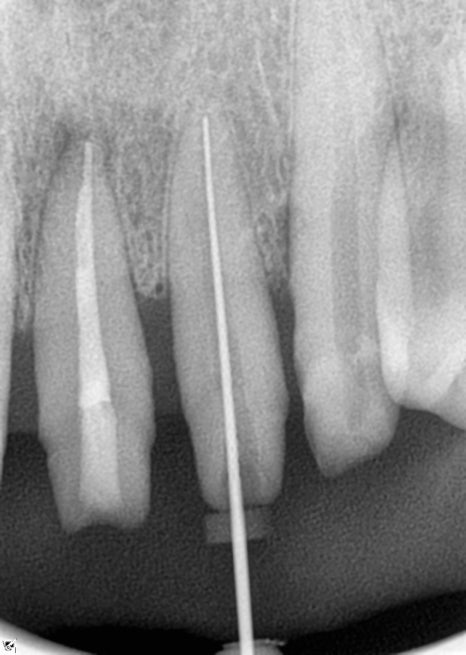

앞니 신경치료

앞니의 경우 보철물 치료를

진행을 할 계획이었는데요

1차 prep 후 환자분이 치아 시림 증상과

불편 증상을 호소하셔서

신경치료를 결정하게 되었습니다.

그 이유는 환자분이 앞니에서의 통증을

호소하셨기 때문인데요.

뿌리가 처음 방문 시부터 워낙 이미 짧기도

했던 부분이기에 신경치료로 진행을

하기로 결정했습니다.